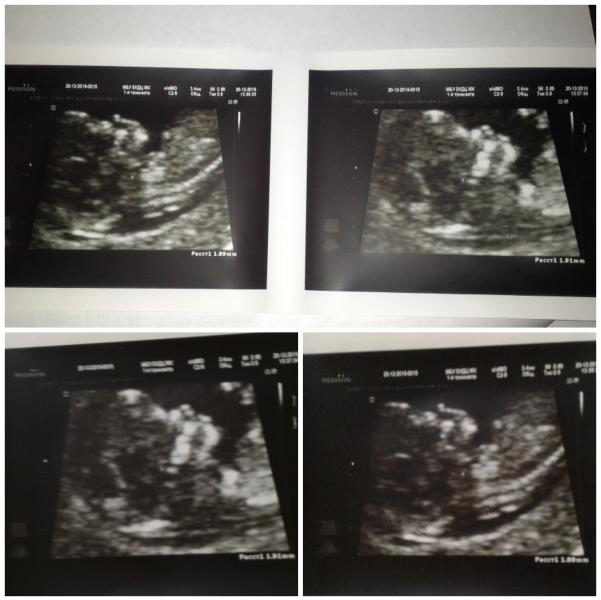

Сегодня прошла наш первый скрининг😍😍😍.

Была в екдц,у своего врача Е.В.Лобановой.

Малыш спал😇👶💘, не хотел показывать личико, лежал спинкой к нам))) Поэтому делали узи дважды👍👍👌👌))))

Послушала сердечко💓💓💓, фото дали посмотреть,показали что гд👌👌👌💜💛💚)))

Сыночек был дома с папо💟💞💟))) и это было очень хорошо, потому что он устал бы))) сначала узи,потом кровь,потом буфет,чтобы разбудить бусинку ,п...